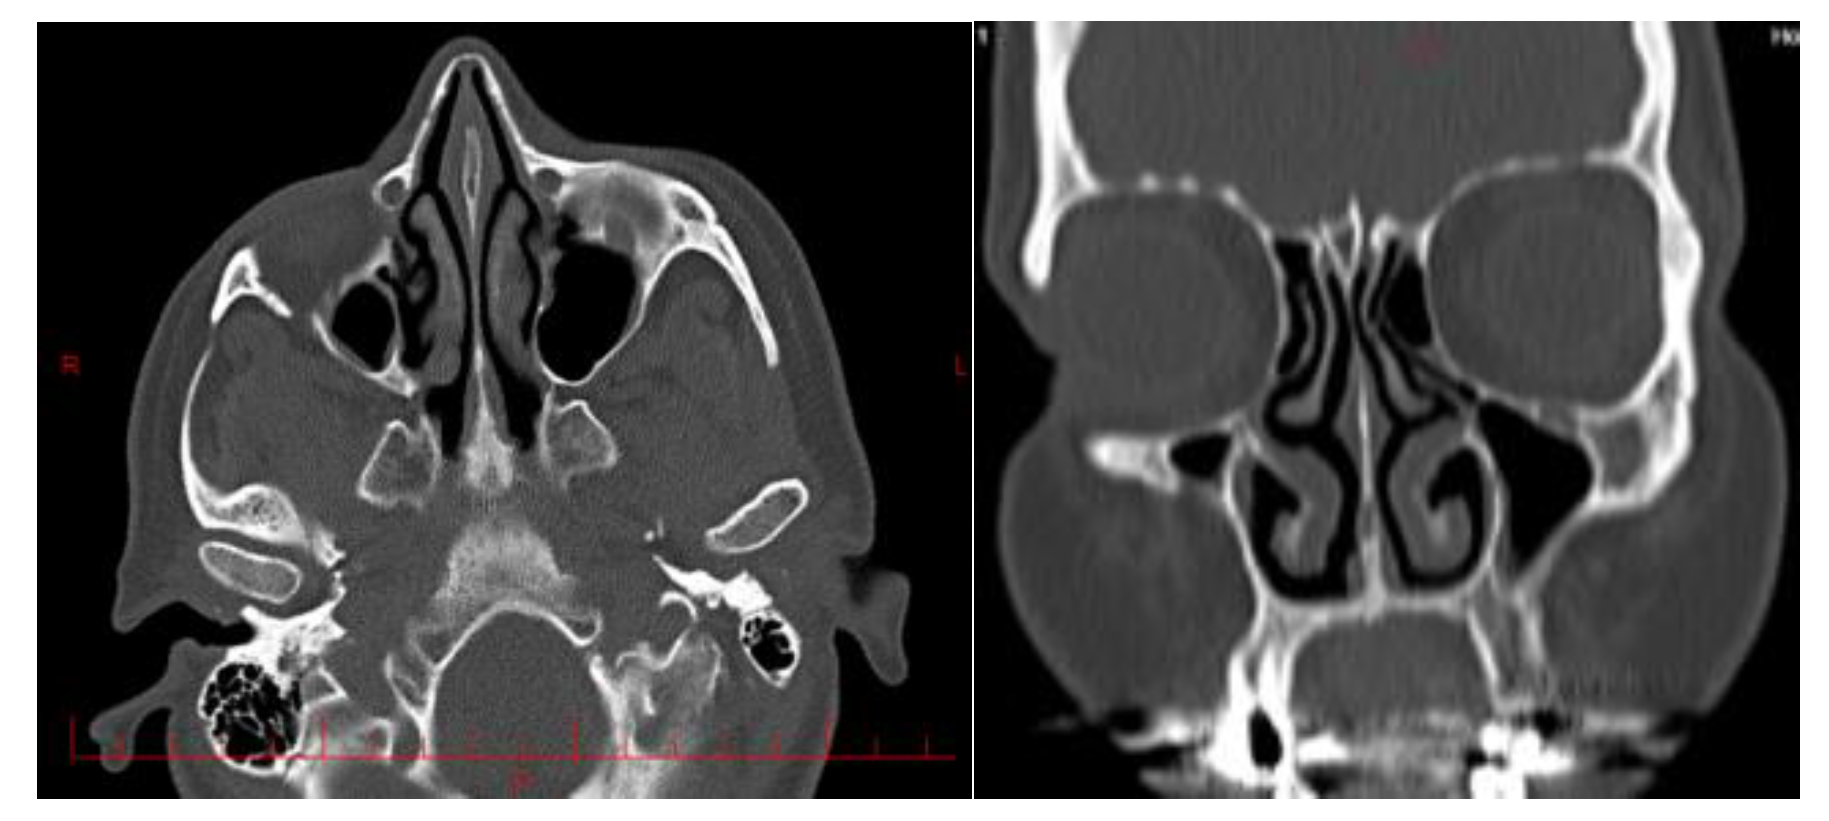

2.1. Geometry reconstruction: